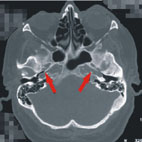

(圖) 箭頭所指為神經內科醫師安排血管超音波後懷疑有內頸動脈硬化,而安排的電腦斷層檢查